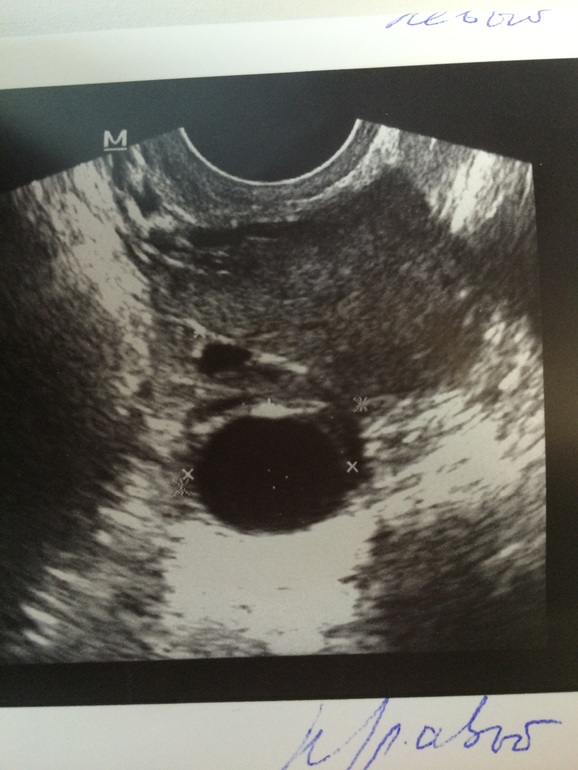

Помогите разобраться! Всё плохо? или есть надежда?

я не узист конечно, но у меня так всегда выглядят фолликулы, ЖТ бывает как-будто изорванное по краям, не ровное...

вот и мне так кажется. я , как нарочно повыкидывала все свои снимки, но как я помню, так и фолликулы и выглядят.

посмотрела — 19 мм. ( приписано с солидным венчиком и ответвления в полости структуры) — читаю и прям какой-то набор слов. Я попросила жидкость  посмотреть она сказала, что вроде не много есть.)

А какой размер этого фолликула и есть ли жидкость сзади матки?Если жидкость есть-вполне может быть это ЖТ(кистообразное).Если нет жидкости и фолликул до 25мм-может вот-вот лопнет тогда.

Если жидкость есть-скорее всего неск.дней назад была овуляция и размер похож на ЖТ.и по описанию-больше на ЖТ похоже.

только на снимке прям вылитый ДФ.

Ну да,похож)Но бывают и ЖТ такие(у меня было такое).Я тоже сомневалась,но врач-узист оказалась права.У Вас выглядит,как кистозное ЖТ .Часто узисты ориентируются именно по жидкости за маткой,т.к.ЖТ может быть похоже на ДФ.

У Вас не киста ЖТ,а кистозное ЖТ,т.е.по виду похоже на кисту.А размер нормальный для ЖТ,киста-это от 25мм.Забейте в инете по поиску кистозное желтое тело фото,будет куча вариантов посмотреть-какие бывают.Я когда сомневалась-так делала.